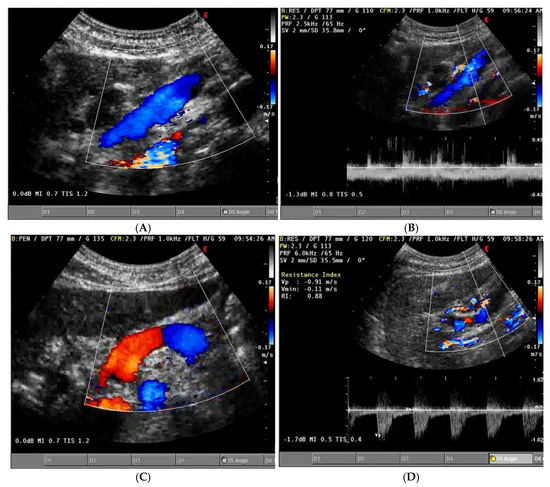

Background/Objectives: Heart failure (HF) causes systemic and regional haemodynamic alterations that extend beyond the heart, profoundly affecting splanchnic circulation. Venous congestion is a hallmark of heart failure (HF) and a major determinant of clinical deterioration and multiorgan dysfunction. The splanchnic venous system—comprising the portal, hepatic, and renal veins—acts as a key reservoir for intravascular volume redistribution. Conventional ultrasound (US), using grayscale and Doppler imaging, offers a direct, non-invasive approach to visualize these haemodynamic changes. This review, Part 1 of a two-part series, summarizes the current evidence and clinical applications of conventional US for assessing splanchnic, cardiac and pulmonary vascular alterations in patients with HF. Methods: A systematic review was performed in PubMed, Embase, and the Cochrane Library up to current date, following PRISMA 2020 guidelines. Eligible studies included adult human investigations evaluating splanchnic vascular changes in HF using B-mode, color Doppler, or pulsed Doppler ultrasonography. Exclusion criteria were pediatric, animal, or non-English studies and non-standard imaging methods. Data on ultrasonographic parameters, haemodynamic correlations, and prognostic value were extracted and qualitatively synthesized; Results: A total of 148 eligible studies (n ≈ 7000 patients) demonstrated consistent associations between HF severity and alterations in splanchnic, cardiac and pulmonary flow. Findings included increased bowel wall thickness, portal vein dilation with elevated pulsatility, and monophasic or reversed hepatic vein waveforms, all correlating with higher right atrial pressure and adverse clinical outcomes. The integration of these parameters into the Venous Excess Ultrasound (VExUS) framework enhanced detection of systemic venous congestion, in addition to the study of the cardiac and pulmonary circulation. Conclusions: Conventional ultrasound assessment of splanchnic vasculature provides valuable, reproducible insight into systemic congestion in HF. Incorporating hepatic and portal Doppler indices into standard evaluation protocols may improve risk stratification, optimize decongestion therapy, and guide management. Further prospective randomized and outcome-driven studies are required before VExUS-based therapeutic thresholds can be universally recommended and define prognostic thresholds. Full article

Figure 1